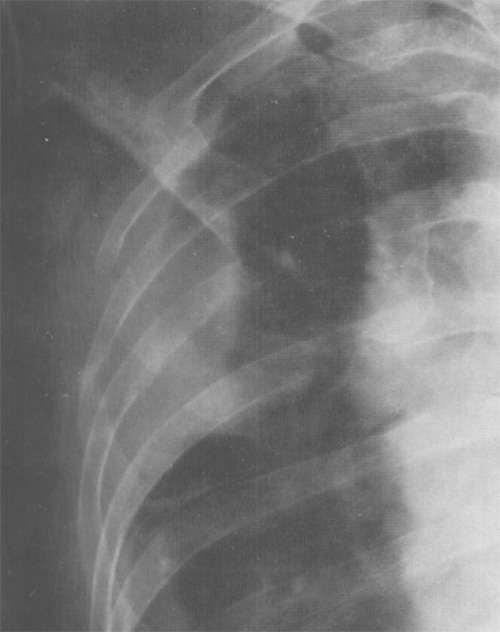

Рисунок 6. Злокачественная мезотелиома плевры с деструкцией прилежащих ребер. Увеличенный фрагмент рентгенограммы в прямой проекции – верхний отдел правого легочного поля)

Злокачественная мезотелиома плевры

Рисунок 7. Злокачественная мезотелиома плевры. Слева отмечается узловое утолщение медиастинальной и реберной плевры